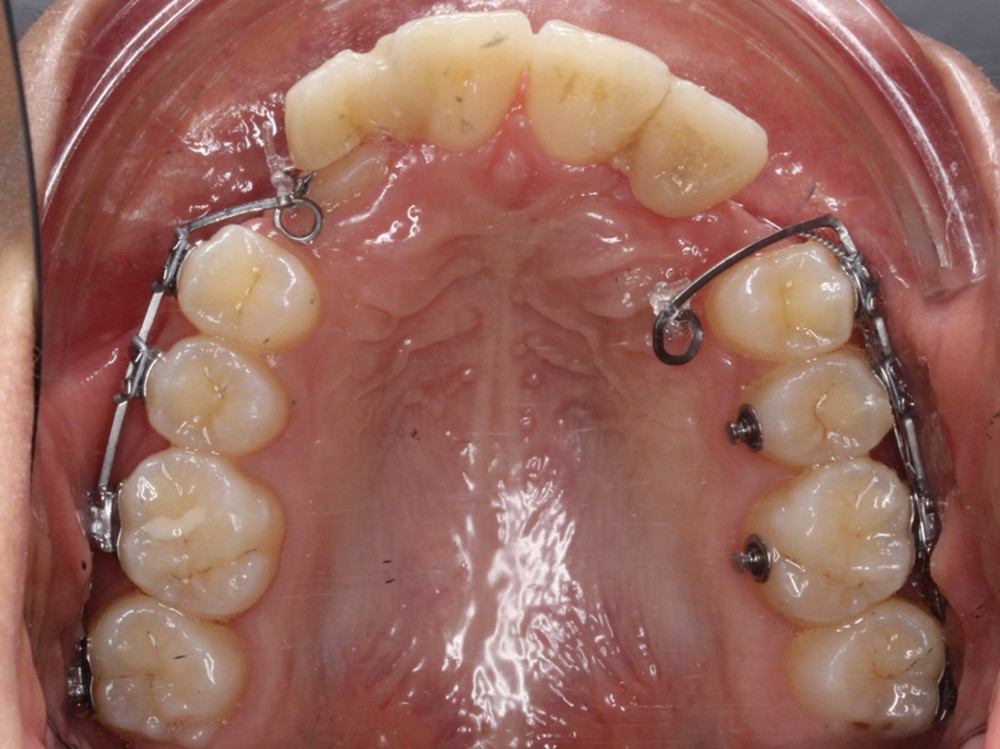

La désinclusion des canines a été réalisée dans un deuxième temps opératoire après trois semaines de cicatrisation muqueuse afin d’avoir une quantité de gencive attachée suffisante lors de la réalisation des lambeaux. Un lambeau déplacé apicalement a été réalisé pour désinclure la 13, avec une direction de traction distale sur une potence soudée sur le sectionnel activée après trois semaines de cicatrisation (fig. 3). Un lambeau muco-périosté repositionné a été réalisé pour désinclure la 23 qui a été immédiatement mise en charge par traction distale sur un bouton palatin collé sur 25. Un approfondissement vestibulaire mandibulaire antérieur a ensuite été réalisé.

La traction des canines incluses s’est faite sur des sectionnels postérieurs en TMA .017 x .025 de type Ballista (fig. 4a,b). Un décapuchonnage de la 23 a dû être réalisé pour lui permettre de transpercer la muqueuse palatine. Des cales occlusales ont été ajoutées pour assurer le passage de la canine de la situation palatine à vestibulaire. Un contrôle radiologique a permis de suivre la traction. Parallèlement, la fermeture des espaces mandibulaires s’est faite par perte d’ancrage postérieure et par redressement antérieur grâce à des chaînettes élastomériques.